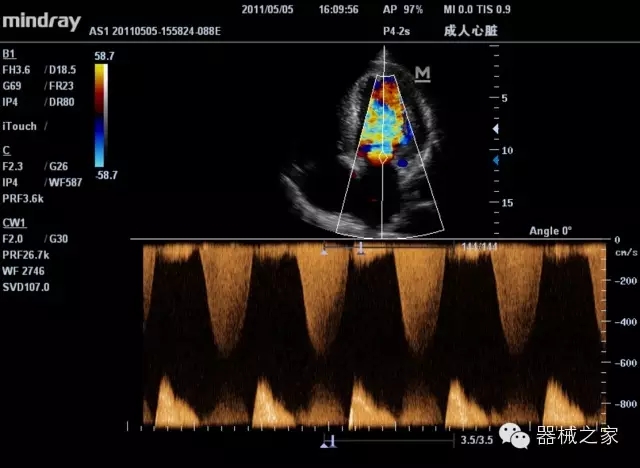

臨床圖片賞析

產(chǎn)品特點(diǎn)